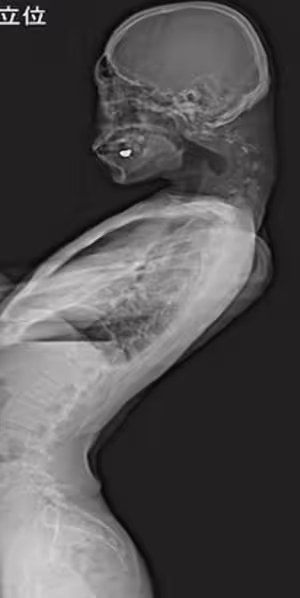

男子長達半年頸部疼痛,甚至抬不起頭,這也導致他吞嚥困難,沒辦法好好吃東西的情況下,體重明顯減輕。他就醫尋求幫助,竟被確診罕見的「頭部下垂症 Dropped Head Syndrome」,X光顯示他的頸椎已變形與位移,還出現一個尖尖的腫塊,看上去就像脖子長了根角。